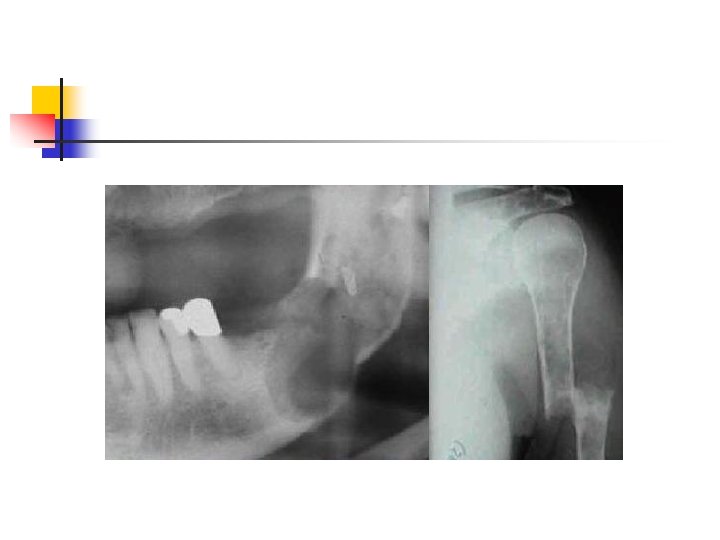

Bisfosfanatlar n n n Pirofosfatların sentetik analoglarıdır 1996 da alendronate osteoporoz tedavisi için onay aldı Osteoklast oluşumunu ve aktivasyonunu inhibe ederler

Bisfosfanatlar n n Osteoklastik kemik rezorbsiyonunu inhibe ederler Mandibula osteonekrozu n n Özellikle zoledronik asid kullanılanlarda Tolidomid + bisfosfonat kullanımında artmış risk

n n 6 aydan uzun süren bifosfanat kullanımı Diş çekimi Periodontal ameliyatlar İmplant operasyonları